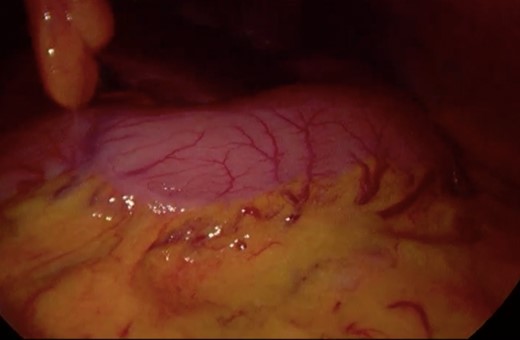

Initially, conservative management was adopted with some improvement of patient’s nutrition condition. However, as symptoms persisted, surgical treatment was recommended. Our surgical approach was a laparoscopic duodenojejunostomy with a latero-lateral stapled anastomosis between jejunum (30 cm from Treitz’s angle) and the second portion of the duodenum (Figs 5–9). The patient recovered with no pain but with a delay in diet acceptance. An upper GI contrast study was performed on the fifth post-operative day revealing a distended stomach with gastric emptying delay, but with unobstructed anastomosis, therefore without stenosis or leaks (Fig. 10). She was discharged home after 8 days with liquid diet and digestive transit restored. After 3 months of follow-up, the patient gained some weight and remained asymptomatic.

Surgery—initial laparoscopic view with distended stomach and proximal portions of duodenum.

Surgery—laparoscopic visualization of the second and third portion of duodenum.

Surgery—laparoscopic stapled anastomosis between jejunum and second portion of duodenum.

Surgery—final laparoscopic surgical view of laparoscopic duodenojejunostomy.